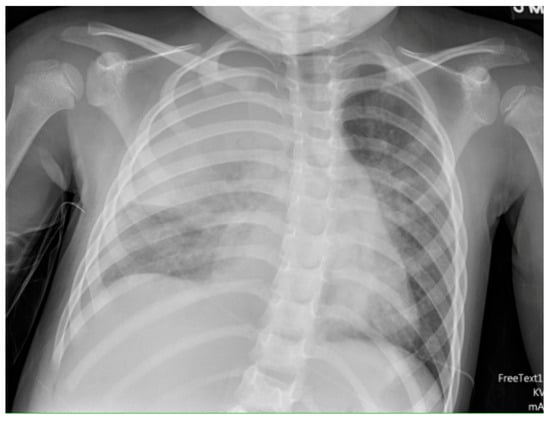

- Huang, W.E.; Matifoll, J.A.; Lord, D.; Haggie, S. A review of imaging in the diagnosis and management of complicated paediatric pneumonia. Paediatr. Respir. Rev. 2025, 54, 12–18. [Google Scholar] [CrossRef]

- Chan, S.S.; Kotecha, M.K.; Rigsby, C.K.; Iyer, R.S.; Alazraki, A.L.; Anupindi, S.A.; Bardo, D.M.; Brown, B.P.; Chandra, T.; Dorfman, S.R. ACR appropriateness criteria® pneumonia in the immunocompetent child. J. Am. Coll. Radiol. 2020, 17, S215–S225. [Google Scholar] [CrossRef] [PubMed]

- Hacimustafaoglu, M.; Celebi, S.; Sarimehmet, H.; Gurpinar, A.; Ercan, I. Necrotizing pneumonia in children. Acta Paediatr. 2004, 93, 1172–1177. [Google Scholar] [CrossRef]

- Tan Kendrick, A.P.; Ling, H.; Subramaniam, R.; Joseph, V.T. The value of early CT in complicated childhood pneumonia. Pediatr. Radiol. 2002, 32, 16–21. [Google Scholar] [CrossRef]